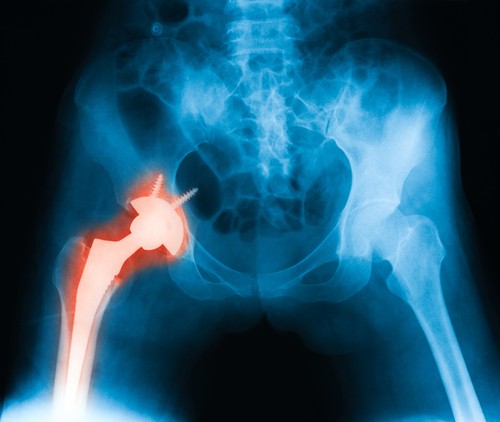

A jövő csontpótlása kinyomtatott implantátummal

Egyedi tervezésű, 3D-nyomtatóval előállítható titán csontpótlásokat fejlesztenek a Debreceni Egyetemen. Az innovatív implantátumokat már nem csavarok tartják, hanem teljesen összeépülnek a csonttal.